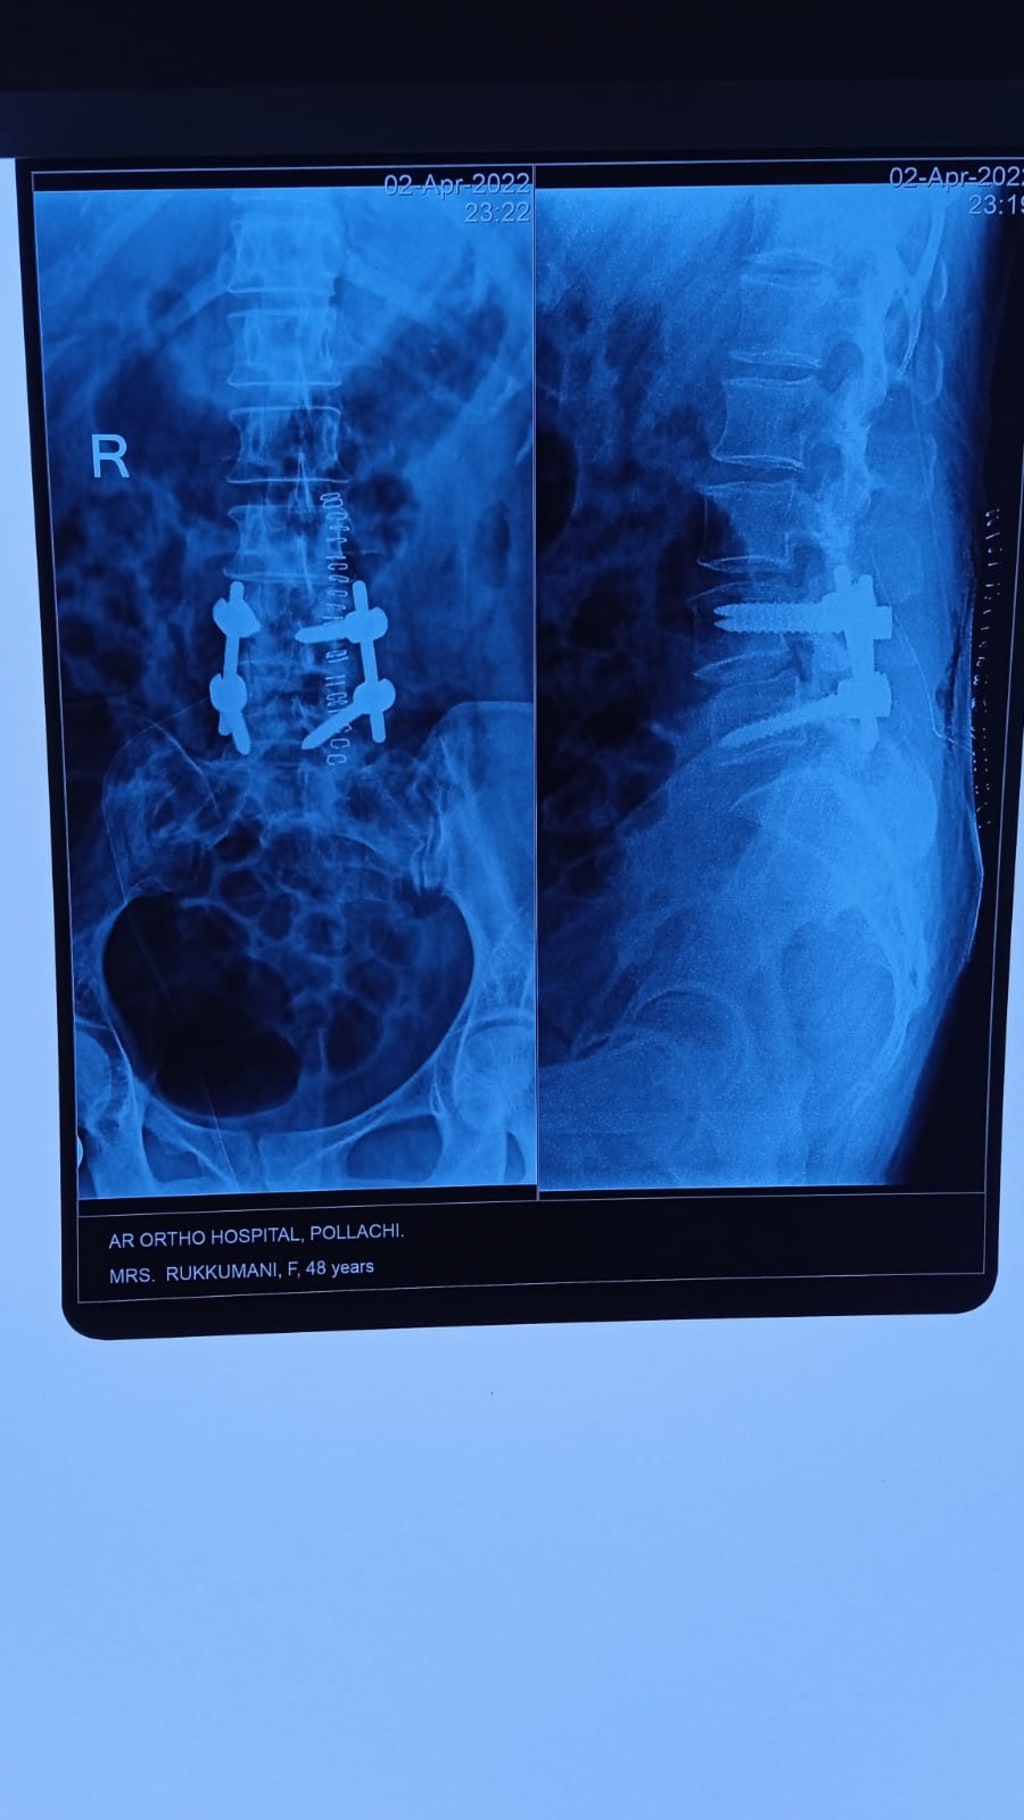

Spine Fixation

A SPINE fracture fixation will fix the bones together to stabilise the spine and relieve pressure on the spinal cord and nerve.